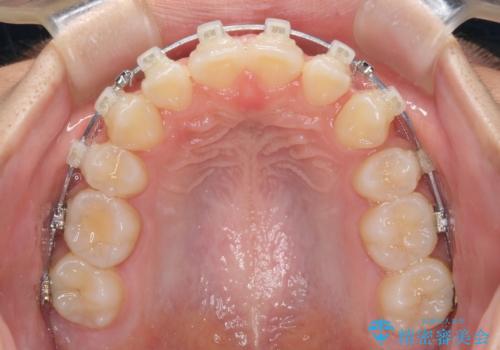

- クリアブラケット

- 2年4ヶ月

- 10-30回

当初は八重歯やデコボコが一番気になっていましたが、抜歯矯正により口元の突出感が改善されるにつれ、口の閉じやすさを実感するようになってきました。

部活動で調整来院に来られないことがしばしばあり、期間は予定よりもかかりましたが、きれいに仕上げることができました。